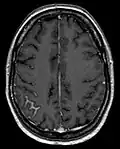

Diagnosis

Screening involves an MRI scan to identify and diagnose tumors in the subarachnoid region of the brain. MRI can make a diagnosis even without an analysis of the cerebrospinal fluid but it can sometimes be difficult to detect because MRI scans cannot always pick up the problem.[20]

Diagnosis is most commonly made by lumbar puncture to detect malignant cells in the CSF, although the tests may be negative in roughly 10% of patients.[5] Diagnosis often requires a high index of suspicion and is confirmed by neuroimaging and cerebrospinal fluid analysis.[21]

CSF examination is the most useful diagnostic tool for NM. Patients with suspected NM should undergo one or two lumbar punctures, cranial magnetic resonance imaging (MRI), spinal MRI, and a radioisotope CSF flow study to rule out sites of CSF block. If the cytology remains negative and radiological studies are not definitive, consideration may be given to ventricular or lateral cervical spine CSF analysis based on the suspected site of predominant disease. Consideration of signs, symptoms, and neuroimaging can help with the placement to where CSF is drawn. Median time of diagnosis from initial primary cancer diagnosis is between 76 days and 17 months.[22]

Techniques

- MRI: Meningeal findings are described with the following characteristics: Nodular meningeal tumor, meningeal thickening >3 mm and a subjectively strong contrast enhancement. A smooth contrast enhancement of the meninges was judged to be typical for inflammatory, nonneoplastic meningitis.[23]

Meningeal carcinomatosis in a patient with breast cancer (contrast-enhanced axial T1-weighted MRI)

Meningeal carcinomatosis in a patient with breast cancer (contrast-enhanced axial T1-weighted MRI)